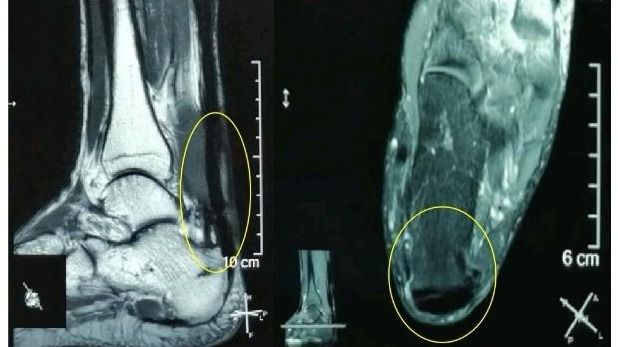

“感谢伍教授!我的跟腱疼痛、肿胀基本缓解了,踝关节活动也好多了,跑步也轻松了!”49岁的郑先生(化名)在电话中连声道谢。在跟腱断裂后,尽管做了修补术,但在半年多的时间里,他因跟腱疼痛、肿胀、踝关节活动受限而苦不堪言。幸好,在开云下注(中国)官网孙逸仙纪念医院康复科副主任伍少玲教授的帮助下,他接受了“超声引导下...